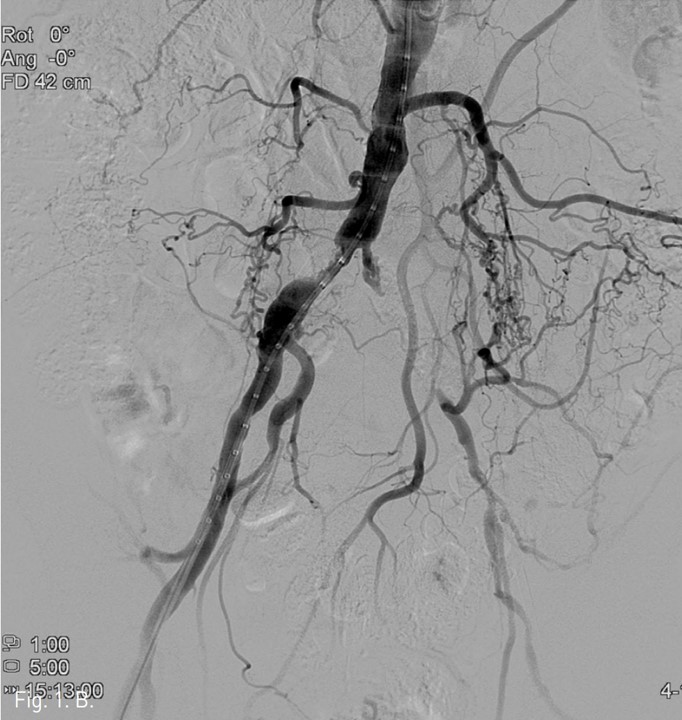

컴퓨터단층촬영 혈관조 영술과 고식적 혈관조영술에서 우측 총장골동맥에 석회화를 동반한 80%정도의 심한 협착이 있고, 좌측 총장골동맥에서 외장골동맥에 석회화를 동반한 완전 폐쇄의 소견이 있다 (Fig. 1A, IB). 우총대퇴동맥의 근위부에 10mm x 29mm Zenesis stent를 설치하였다 (Fig. 2). 0.035 inch guidewire로 좌측 총장골동맥의 기시부 폐쇄부위 통과를 시도하였으나 가성내강에서 진성내강으로 재진입이 되지 않았다 (Fig. 3). 좌측 외장골동맥 진성내강 내에 있는 ‘L-자’ 표시방향의 outback device가 보인다 (Fig. 4A), 좌측 외장골동맥 진성내강 내에 있는 'T-자’ 표시방향의 outback device가 보인다(Fig. 4B). Outback device를 이용하여 동맥내막을 천자후 0.014 inch guidewire를 가성내강 내로 진입시켰지만 좌측 총장골동맥-외장골동맥경 계부위에서 더 이상 진행되지 않았다 (Fig. 4C). 0.014 inch guidewire를 따라서 Davis catheter를 가성내강 내로 진입시키고 (Fig. 5A), 10mm snare를 삽입하여 Simmon catheter내부에 있던 microwire를 전진시켜 snare로 잡아 좌측 sheath로 뽑아내어 (Fig. 5B), 5Fr. Davis catheter를 대동맥 내부로 진입시켰다(Fig. 5C). 양측 총장골동맥 및 좌측 외장골동맥 스텐트 설치후 대동맥장골동맥조영술상에서 양측 장골동맥의 완전한 재개통을 보인다 (Fig. 6).

시술 후 대동맥장골동맥조영술상에서 양측 장골동맥의 완전한 재개통을 보인다.

Fig. 6.

Fig. 6. Completion pelvic arteriography shows complete recanalization of both common iliac and left external iliac arteries.